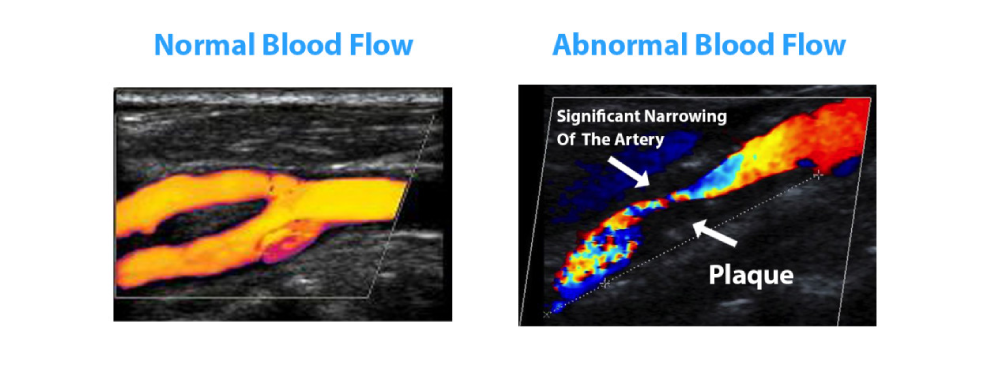

A Carotid Doppler test is a specialized ultrasound scan that uses sound waves to evaluate the structure and blood flow of the carotid arteries. These arteries are vital because they carry oxygenated blood from your heart to your brain. Over time, factors like high cholesterol, high blood pressure, smoking, diabetes, or even genetic predisposition can lead to plaque buildup inside these arteries, a condition called atherosclerosis. This buildup may cause narrowing (stenosis) or blockages, which significantly raises the risk of stroke.

Unlike imaging procedures that require radiation exposure or contrast dyes, the Carotid Doppler test is completely safe for people of all ages. During the test, the Doppler technology captures both structural and functional data — not only showing the shape of the arteries but also measuring the speed and direction of blood flow. This combination allows radiologists to detect even subtle issues before they progress. At Insight Diagnostics Pallavaram, our advanced machines and skilled professionals ensure that every patient receives a precise evaluation, making this scan an invaluable tool in preventive healthcare.

The Carotid Doppler ultrasound is one of the most reliable tools to diagnose vascular conditions before they become life‑threatening. It is widely used to detect carotid artery stenosis, a condition where plaque buildup narrows the arteries, restricting blood flow to the brain. It also helps identify blood clots, which can cause sudden blockages, and aneurysms, where a weakened artery wall bulges, increasing the risk of rupture.